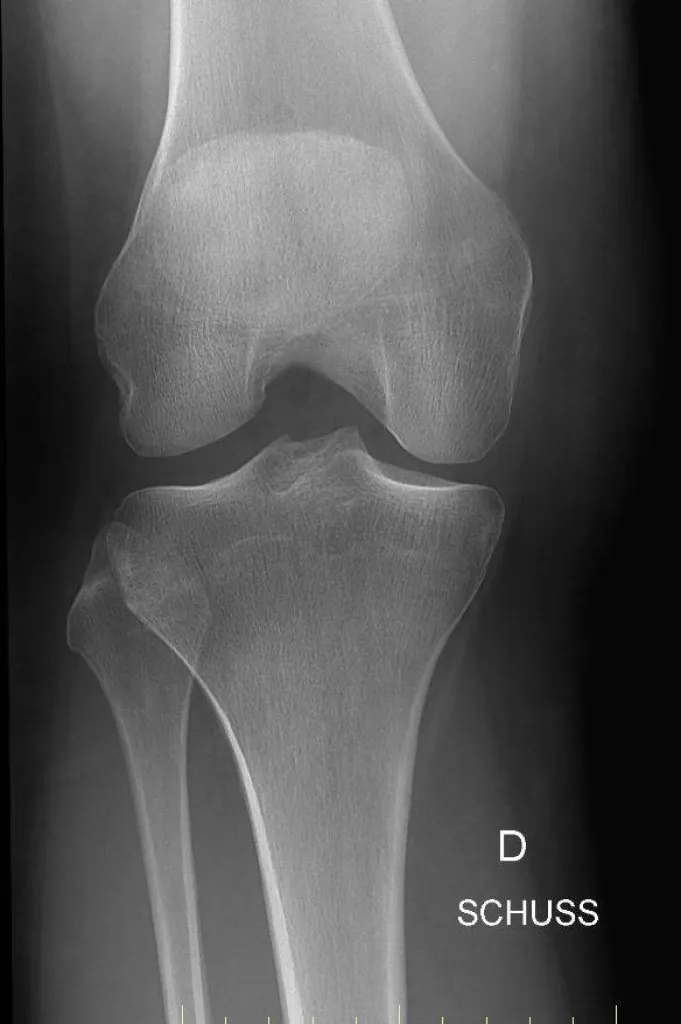

Genou de face

Faire une radiographie du genou dans notre centre d'imagerie médicale à Marseille

Les rayons X sont utilisés en première intention pour le diagnostic des douleurs de genou. Mais également pour le traumatisme et la recherche de corps étranger. Cet examen est indolore. Nous utilisons les machines de dernières génération, numérique, dites "capteur plan".Nous vous accueillons dans ...